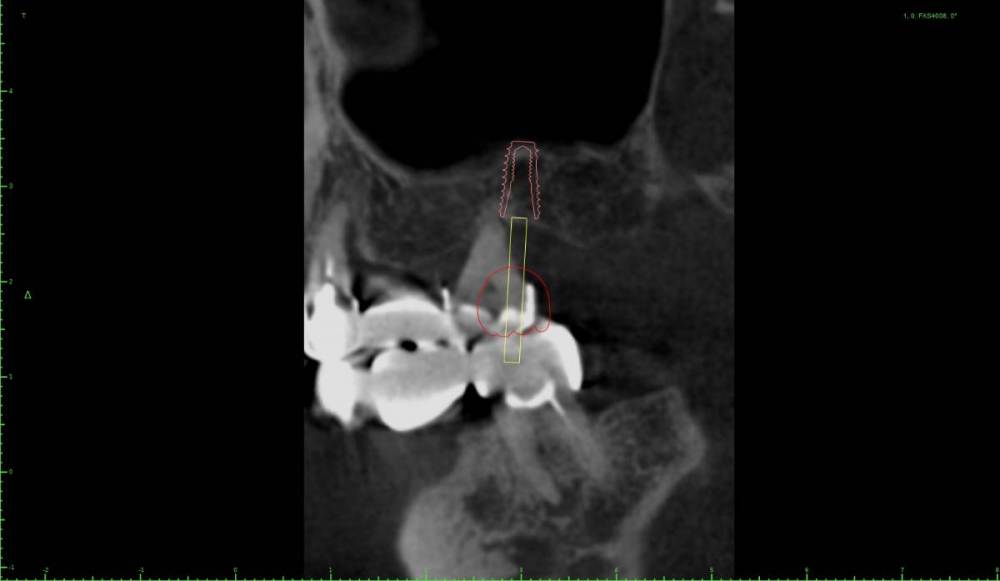

Женька Опубликовано 17 октября, 2021 Поделиться Опубликовано 17 октября, 2021 Перелом под десну, рядом мост 2.5-2.7, который конечно же пациент менять не хочет. Смущает дефект между клыком и 2.4, переходящий на вестибулярную пластинка 2.4. Как решали бы? Возможно только мягкими тканями закрыть? Пошли бы одномоментно или законсервировали бы? Ну и ангуляция имплантата, приемлемое ли положение для ортопедии выходит? Ссылка на комментарий

Женька Опубликовано 21 октября, 2021 Автор Поделиться Опубликовано 21 октября, 2021 Хотя если планировать вот так, то вроде и не всё так уж страшно? Ссылка на комментарий

Женька Опубликовано 27 октября, 2021 Автор Поделиться Опубликовано 27 октября, 2021 @Фаик Исламбеков пока только получил согласие пациента на снятие моста, одномоментную установку вот в таких позициях. Буду делать одномоментно, факап может только с 2.7 случиться кмк... в случае чего ушьём и зайдем через 2-3 месяца. 1 Ссылка на комментарий